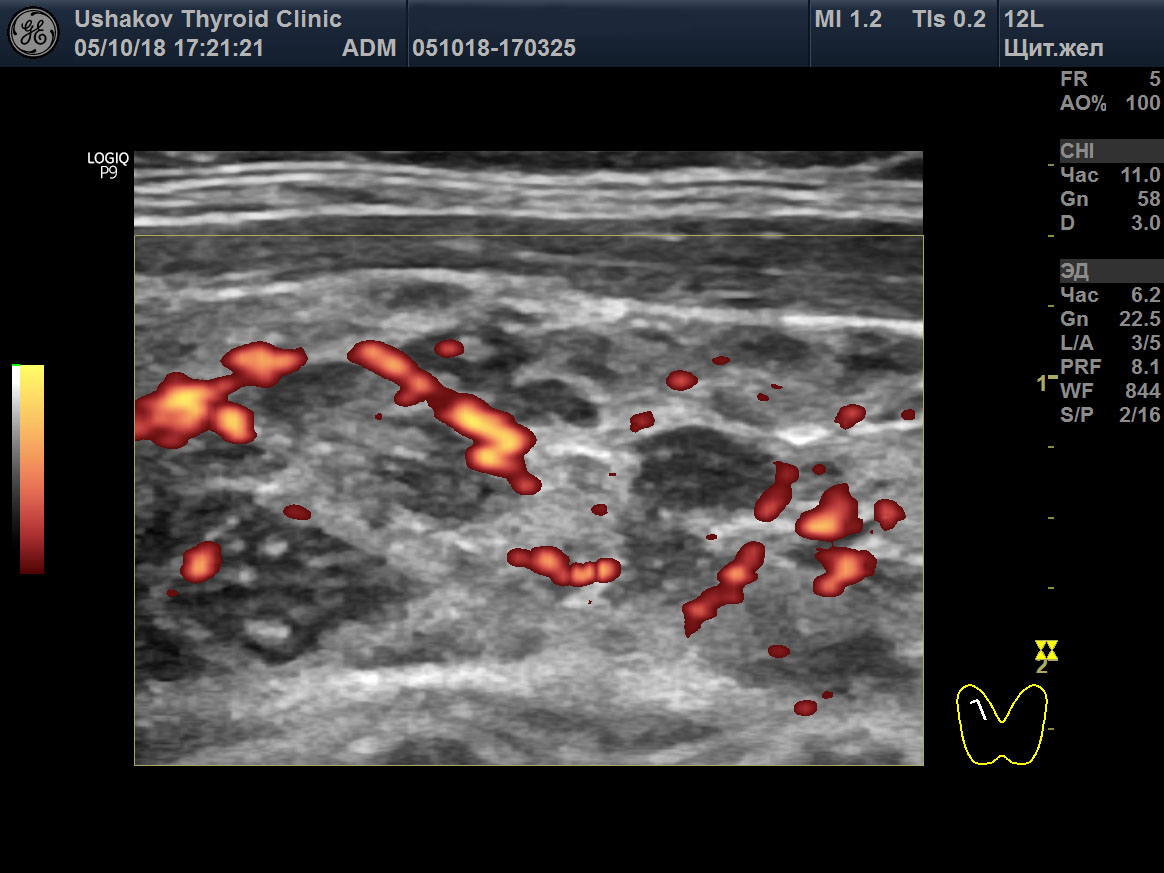

|

Рисунок 2 (окончание) В режиме ЭДК определяется умеренное усиление интенсивности кровотока.